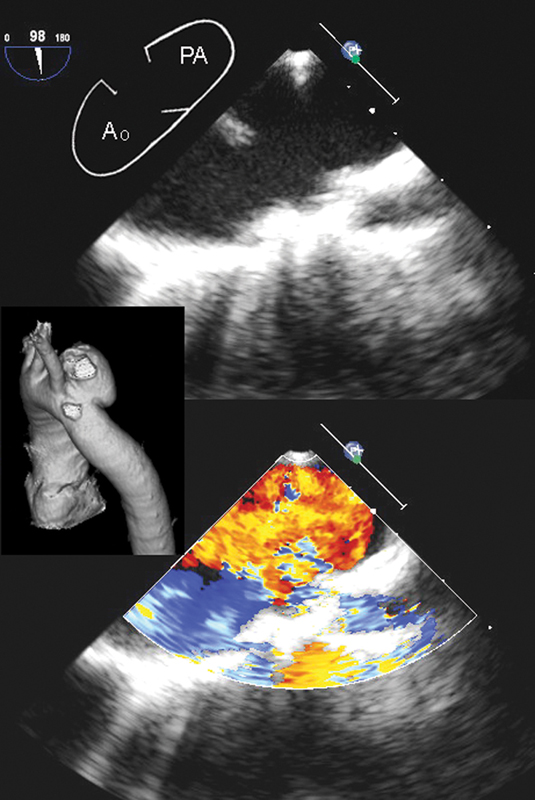

فحوصات تشخيصية لبعض امراض القلب والشرايين التاجية